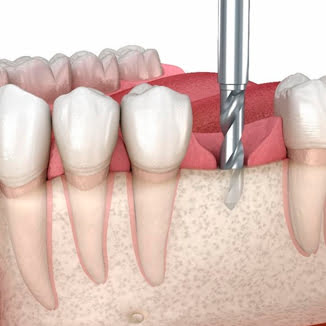

We provide in-depth clinical education and training, including courses on implants, bone grafting, and soft tissue surgery.

We offer specialized seminars for dentists, covering implant placement, bone grafting, soft tissue surgery, and restoration. Each course combines lectures, hands-on workshops, and live demonstrations to ensure practical learning.

- fundamentals of implant placement and surgical grafting

- advanced methods of bone augmentation and planning

- soft tissue procedures for aesthetic outcomes